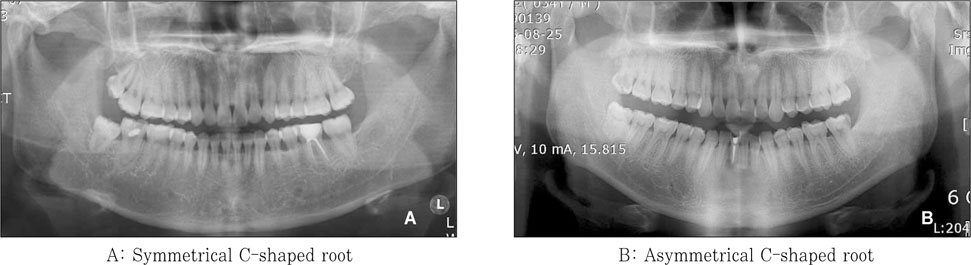

Figure 4

Bilateral symmetry of the C-shaped root canal.

jkacd-32-335-g004.jpg

Figure 4 Bilateral symmetry of the C-shaped root canal.